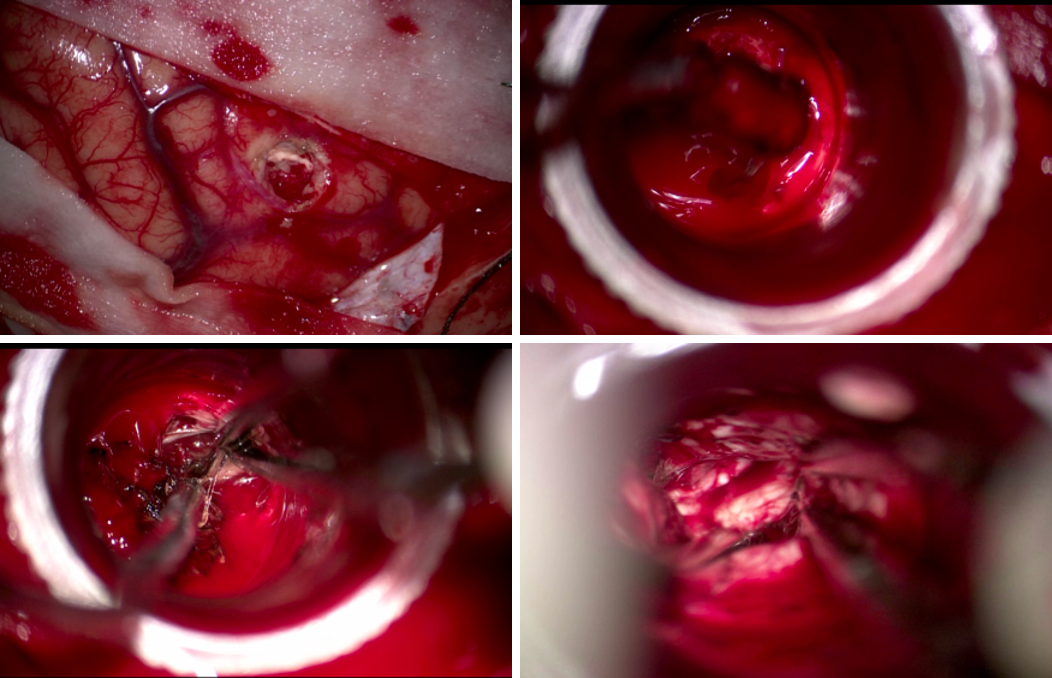

与其他可用于深部动脉瘤治疗的微创方法相比,endoport辅助显微外科具有一定的优势。首先,endoport的优势是微创:皮层造瘘中,endoport的光面结构能有效地减少造瘘通道皮层的挫伤,从而减少了对脑组织的继发损伤。其次皮层造瘘口稳定,减少了人为使用脑压板过程中造成的造瘘口撕裂。然而endoport也存在相应弊端[7],钙化病变和直径大于3厘米的病变可能难以通过endoport切除。

在本例病例中,针对脑室内动脉瘤,我们首选血管内治疗栓塞脑室旁动脉瘤,因为血管过于迂曲尝试失败。术后出现脑室内出血,于是启动备选方案,急诊在磁共振导航下通过endoport辅助进行动脉瘤切除,同时部分清除脑室内血肿并放置脑室外引流,降低远期脑脑积水的风险。随着神经内镜的普及,深部的脑血管病变的治疗方案有了更多的选择,而充分的术前评估与周全的手术方案规划是手术安全与成功的基石。